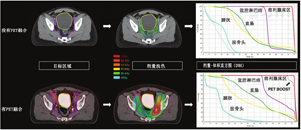

在计划前,放射肿瘤学家首先勾画出总靶体积和疑似隐匿性肿瘤区域(CTV)。考虑日常每例患者剂量设置的误差,最终靶区(计划肿瘤体积)往往是CTV的等距扩展。风险器官(如膀胱、直肠)也会被描绘出来。放射肿瘤学家的目的是在不损害周围器官功能的情况下,对肿瘤进行尽可能高的剂量照射。现代治疗计划利用了患者体位固定系统、动态多叶准直器、逆向规划技术和计算机剂量投送。最终的结果是给靶区(CTVs和计划肿瘤体积)的剂量具有高度适形和可重复性,并恰当避免对邻近正常组织和器官(特别是风险器官)的影响。因此,准确绘制恶性肿瘤组织本身是提升现代放疗疗效的关键限制因素。治疗计划通常以CT为基础,因为计算其精确剂量所需的电子密度可以从Hounsfield单位中推断出来。为了辅助目标轮廓圈定,可以通过基于交互信息的图像配准,将其他成像方式如MRI和PET/CT融合到专用的规划CT扫描中,以辅助目标的描绘。根据这些图像确定规划目标,并将生成的目标轮廓回传至专用的规划CT进行治疗规划(图1,图2)。

单独放疗或联合激素治疗是局部前列腺癌的可能治愈方法,也是根治性前列腺癌切除术后复发性前列腺癌可能治愈的SRT方法。值得注意的是,CT上通常看不到大体前列腺肿瘤。MRI可发现前列腺内的肿瘤病灶,具有良好的灵敏度[48],但多数前列腺肿瘤为多灶性,部分隐匿病灶在MRI上不可见[49]。因此,在确定的情况下,CTV包括整个前列腺、包括或不包括精囊和盆腔淋巴结,这取决于临床病理特征。图1A显示了1例典型的低危至中危前列腺癌患者的CTV和风险器官。医师给予患者前列腺的剂量比淋巴结的要高(如果包括的话)。在挽救性治疗组,CTV是前列腺窝和精囊残余物,包括或不包括盆腔淋巴结。图1B显示了复发性前列腺癌患者接受SRT的CTVs和风险器官,包括选择性盆腔淋巴结的覆盖。SRT靶区体积通常是在没有复发性疾病的影像学证据情况下绘制的。在实际中,大多数医师的CTVs建立是基于已发表的共识指南。放疗肿瘤组(Radiation Therapy Oncology Group, RTOG)已发表了盆腔淋巴结指南[50]。RTOG[51]、欧洲癌症研究和治疗组织[52]、澳大利亚和新西兰放射肿瘤学泌尿生殖组[53]发表了勾画前列腺床区轮廓的指南。这些共识CTVs正用于当前临床试验并指导常规护理。

与PET/CT结合可能在许多方面影响放疗计划。首先,在PET/CT定义的目标体积内总体疾病可以给予更高剂量。图2显示了1例复发性前列腺癌患者的典型SRT计划,以及1例68Ga-PSMA阳性的左侧髂内淋巴结接受的剂量高于周围盆腔淋巴结患者的SRT计划。剂量显示为热图。剂量-体积直方图显示了涵盖每个描绘体积的给定百分比剂量。图中显示,68Ga-PSMA阳性淋巴结(加上边缘)100%接受超过65 Gy(图中虚线),而整个盆腔淋巴结体积100%接受45 Gy(图中紫色实线)。